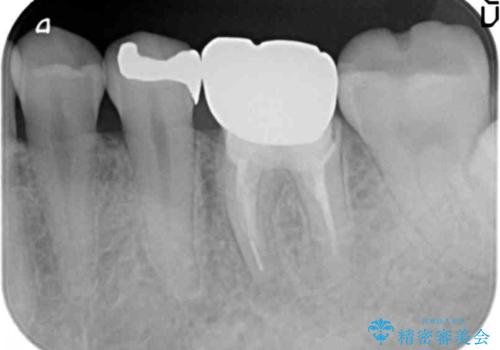

抜歯後、骨の再生を待ったことで、清掃性の高い位置に埋入を行い機能的・審美的なインプラント治療を行うことができました。

- 44万円(インプラント・チタンカスタムアバットメント・ジルコニアクラウン・仮歯)費用は治療当時の料金となります